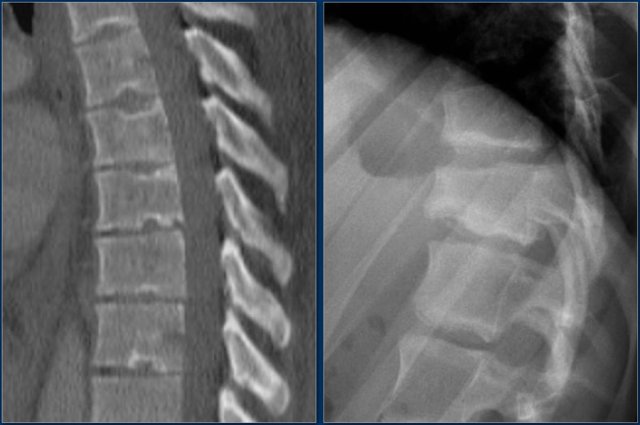

The axial CT and MRI in the same patient show the displaced fragment pressing on the thecal sac.

On the sagittal CT and MRI there are no signs of posterior ligamentous injury.

The anterior longitudinal ligament is disrupted.

The right facet joint looks a bit widened on the CT and there is some fluid in the joint on the MRI.

If there was a lot of fluid in the joint, we should call this indeterminate.

In this case we are not sure.